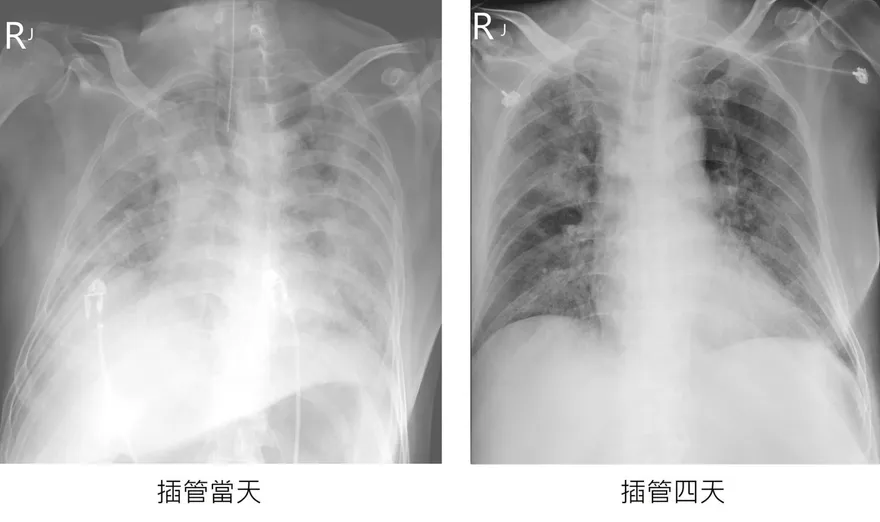

肺浸潤

大白肺